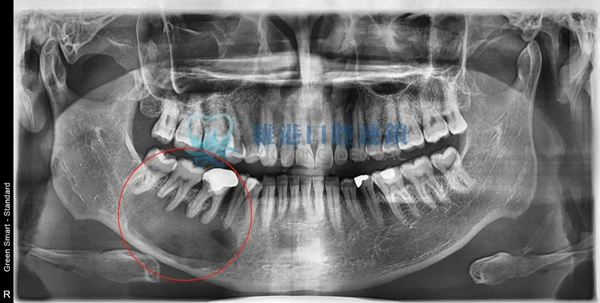

嚴重案例